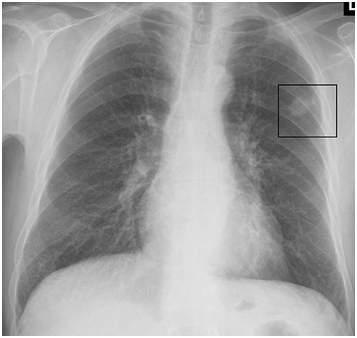

Oko 10% ljudi sa karcinomom pluća nemaju simptome pri dijagnostici, ovakvi

kanceri se slučajno otkrivaju pri rutinskim radiografskom pregledu grudnog

koša.

Radiografija pluća - Ovo je jednostavan i brz test koji

može da pokaže lokalizaciju, veličinu i poziciju tumora. Ponekad je ovo

nedovoljan pregled jer cesto ne dobijamo dovoljno informacija o tumoru

a ne tako retko možemo dobiti normalan nalaz koji ukoliko su prisutni

simptomi zahteva dodatne dijagnostičke postupke.